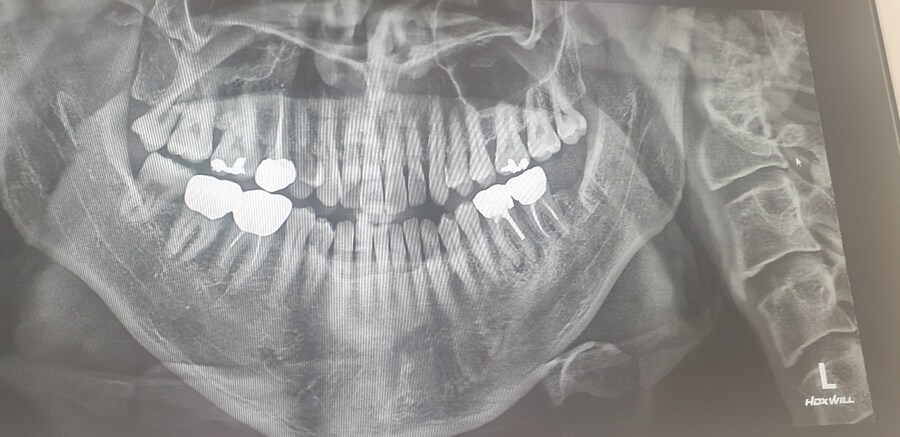

[잡설 ] 사랑니 발치 하고 왔습니다. 2일차 2025.05.08 PM 02:20

잇몸에 매복해 있거나 누어있다면 .. 좀 위험하지요

왼쪽 아래 36번치아 확인해보세요